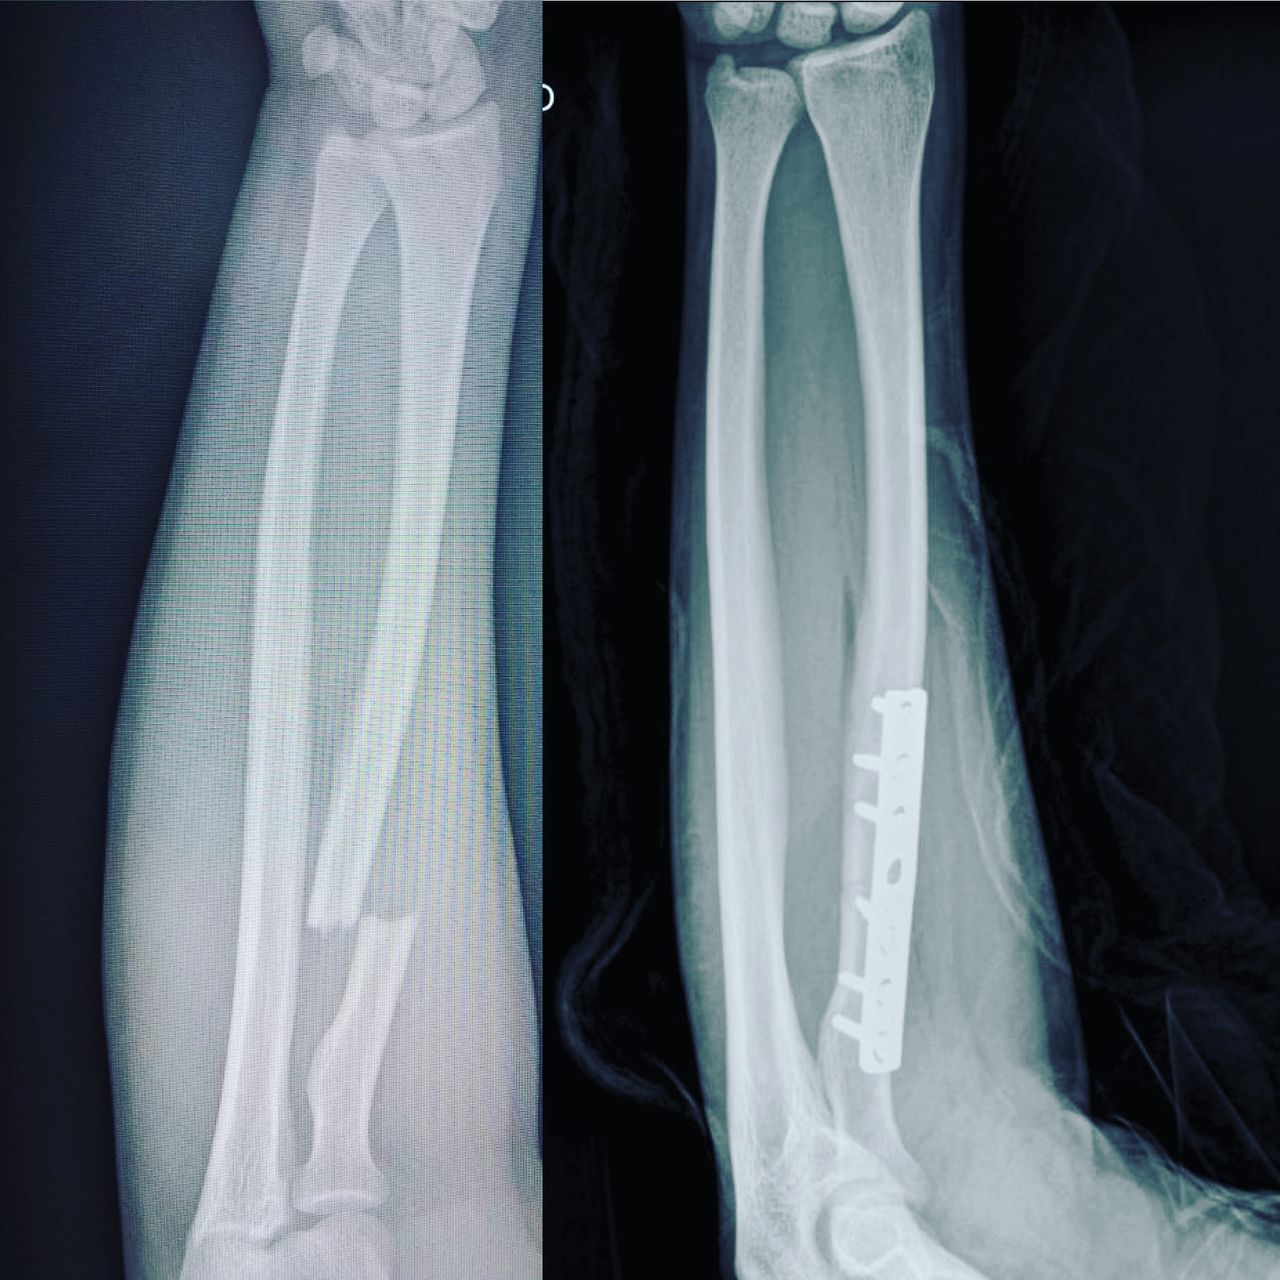

Fotos y videos